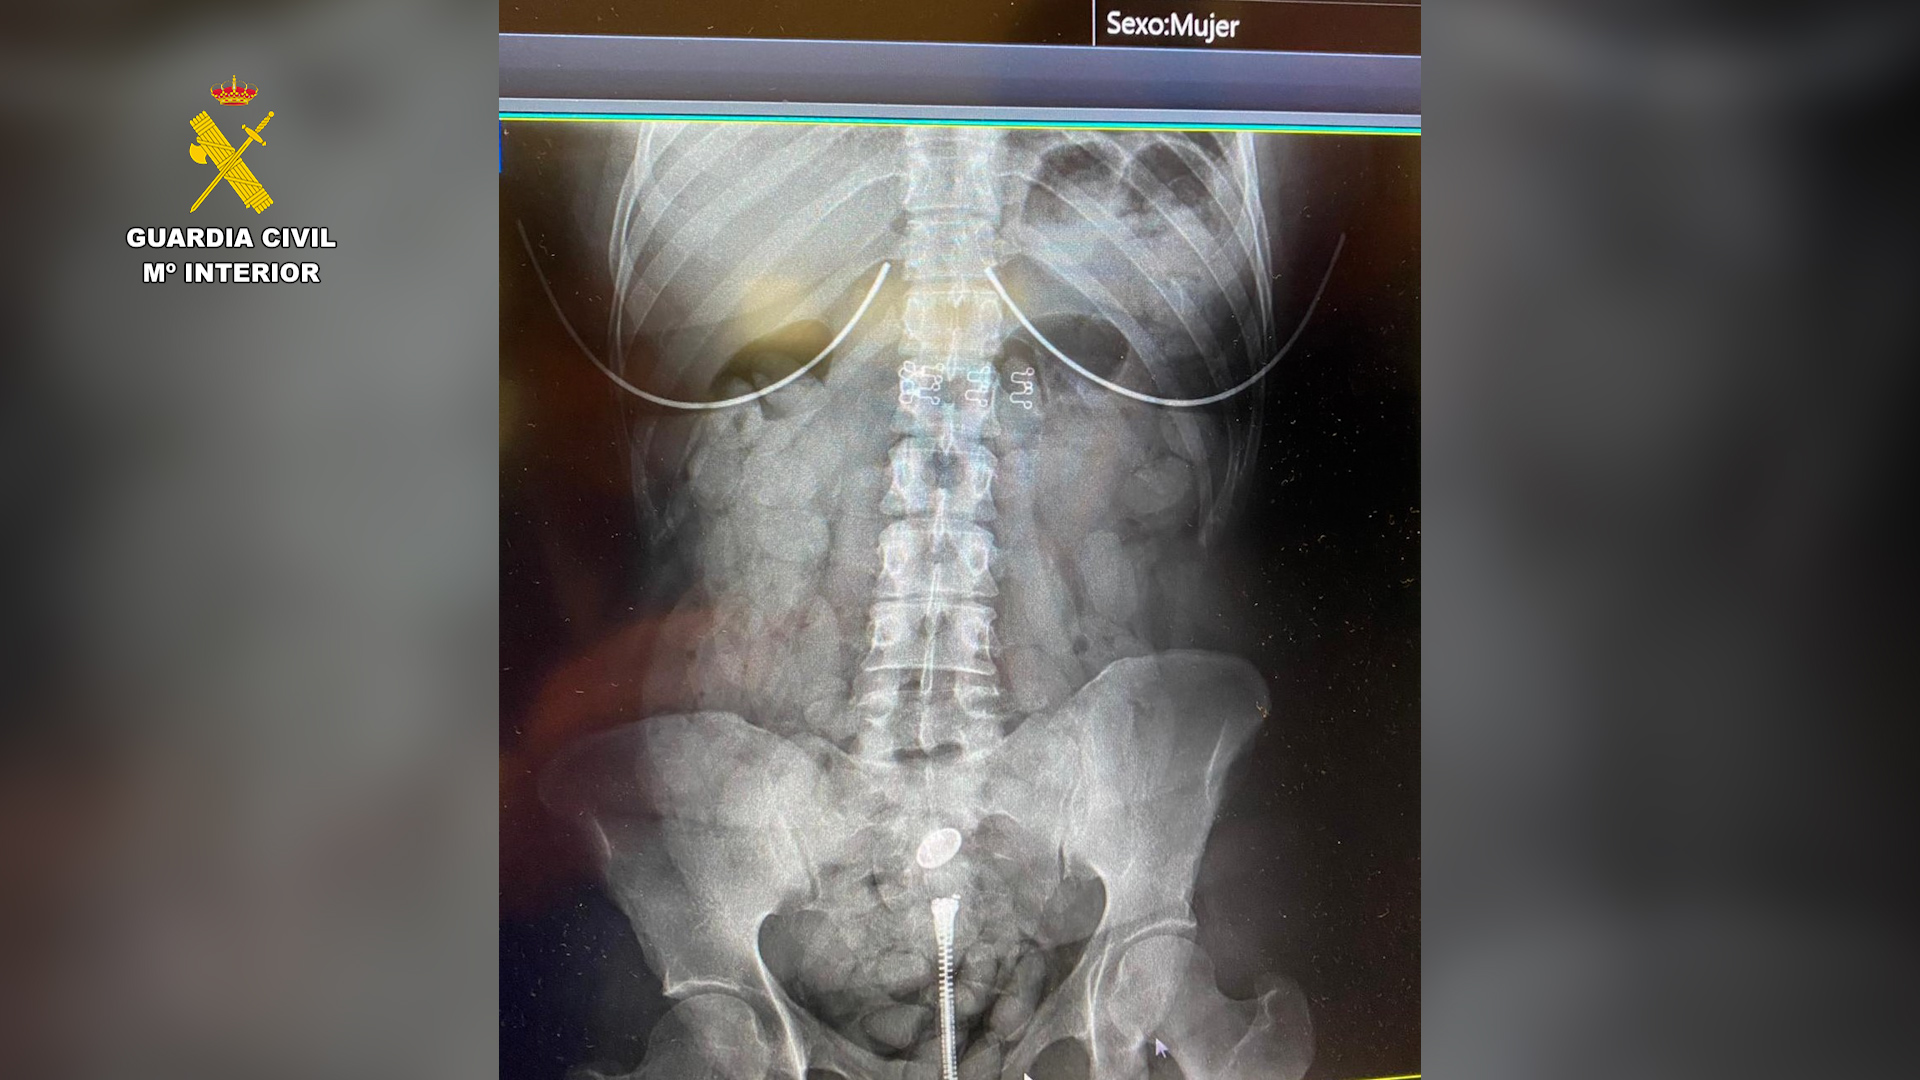

Posteriormente y dadas las sospechas, las tres personas mayores de edad fueron sometidas a pruebas radiológicas en un hospital, dando como resultado que todos habían ingerido sustancias extrañas y que las portaban dentro de su organismo.

Por tal motivo, los tres mayores quedaron ingresados y detenidos en el hospital al padecer un grave riesgo para su vida por obstrucción intestinal.

Cabe destacar, que en el interior del organismo, portaba cada uno de ellos unas 100 bellotas de hachís, con un peso aproximado de 1 kilogramo. Cada bellota presentaba un tamaño de unos 4 cm y pesa unos 10 gramos.